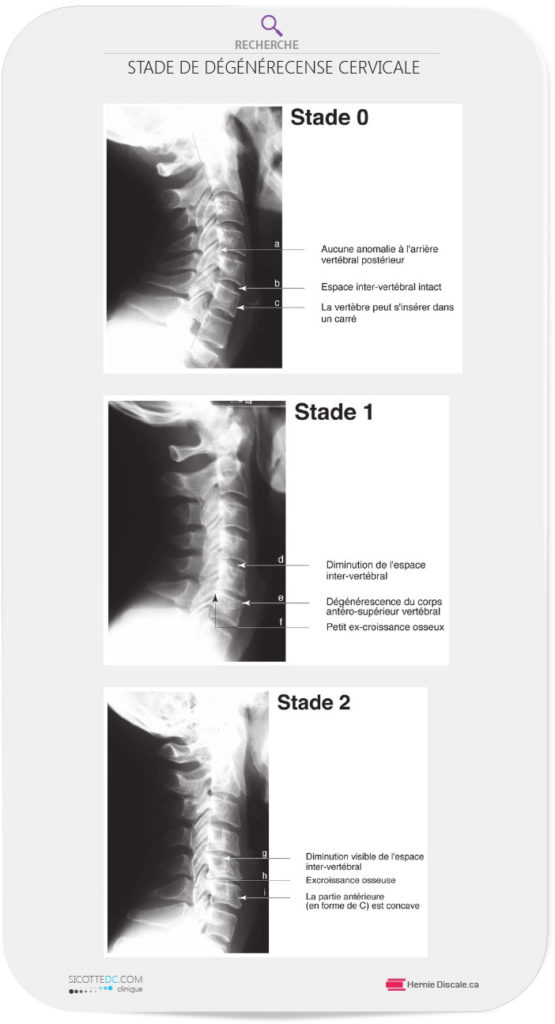

STADE 0

À ce stade, tous les disques intervertébraux sont intacts. La face arrière de la vertèbre (stade 0 (a) ne présente aucun ostéophyte (ces petits bouts d’os dont nous avons parlé plus haut). L’espace intervertébral (b) est épais et intact. Si l’on traçait un carré imaginaire, toutes les vertèbres pourraient s’y insérer (c).

STADE 1

La diminution de l’espace intervertébral est minime, mais présente (d). Un oeil non habitué pourrait difficilement faire la différence. Lentement, la face avant de la vertèbre commence à s’éroder (e). Ceci est souvent dû à la perte de courbure cervicale. Cette perte augmente le poids sur la face avant de la vertèbre (stade 1 (b), produisant ainsi des becs de corbeau (ostéophytes). L’apparition même minime de ces ostéophytes devient évidente (f).

STADE 2

L’amincissement du disque se visualise bien (g). Les ostéophytes sur la face arrière sont d’avantage visibles à cause de cette augmentation de la blancheur de l’os (h). L’os se situe dans une zone de pression croissante. La face avant de la vertèbre devient concave (i). La vertèbre ne pourrait plus s’insérer parfaitement dans un carré…

STADE 3

L’engorgement du canal vertébral par des ostéophytes sur les faces arrières des vertèbres est commun (j). La face de la vertèbre se trouve soumise à un stress anormal, ce qui est démontré par l’apparition d’une certaine blancheur juste au-dessus du disque (k). Le ligament longitudinal antérieur montre parfois des signes de calcification (I), ce qui limite le mouvement normal du cou vers l’arrière.

STADE 4

Une subluxation (déplacement mineur) significative de la vertèbre (m) apparaît. L’espace intervertébral est presque inexistant et la face de la vertèbre est déformée (n).

STADE 5

À ce stade, la fusion, est inévitable (o) et elle peut se produire à plusieurs niveaux vertébraux. La description des stades que nous venons de faire est utilisée à notre clinique lors du rapport des conclusions à la suite de votre examen. La dégénérescence est un mal permanent lorsqu’elle a débuté. Elle ne peut pas être éliminée complètement.